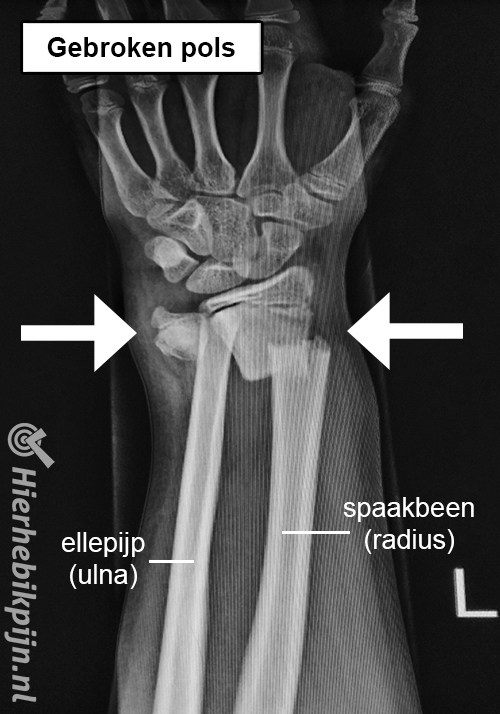

Botbreuken